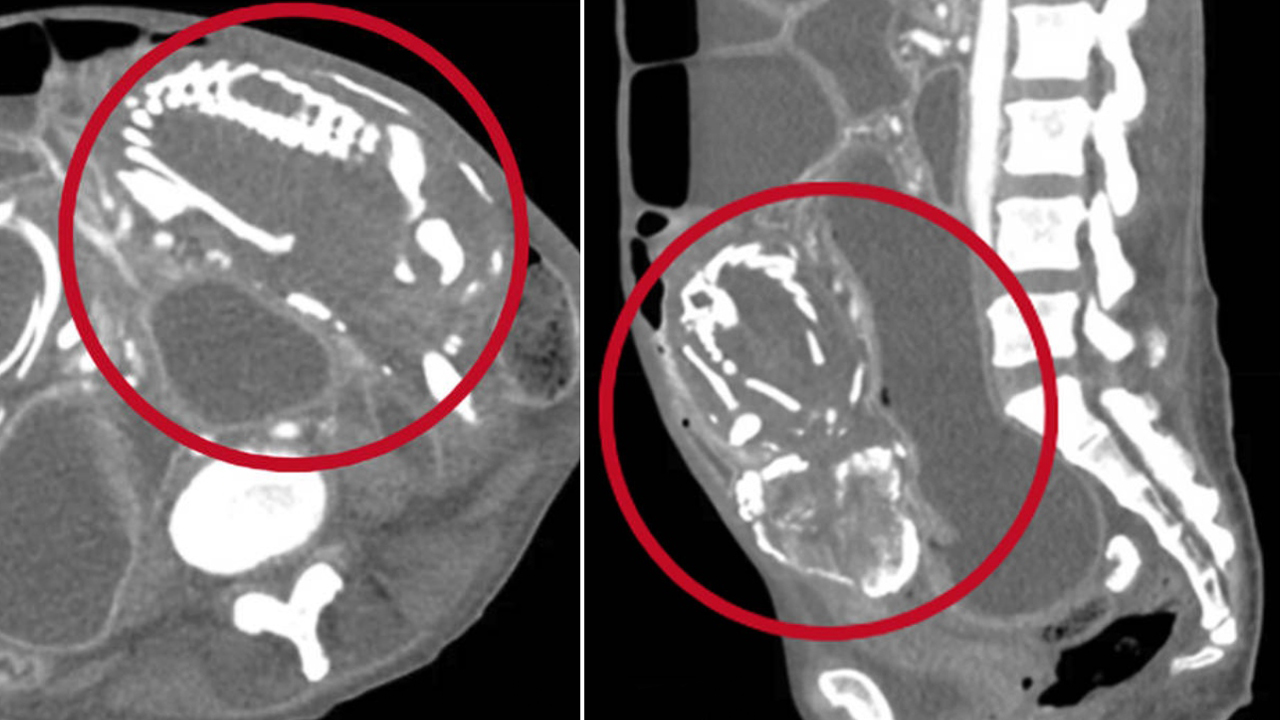

En Nueva York, una mujer de 50 años murió por desnutrición, después médicos se dieron cuenta al realizar varios exámenes que tenía un feto momificado incrustado en su abdomen. Aseguran que llevaba nueve años en su abdomen.

Según un medio local, el bebé tenía el tamaño de una lechuga, lo que generó una obstrucción en sus intestinos.

Esta obstrucción hizo que sufriera de desnutrición y posteriormente la muerte.

Foto tomada de Twitter @LBCNews